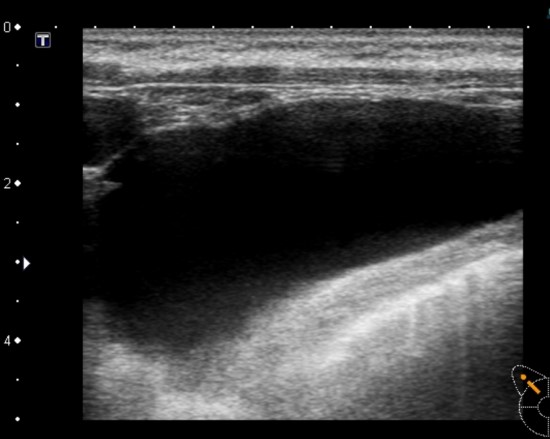

하지만 높은 비용의 MRI를 반복적으로 촬영한다는 것은 경제적 부담이 되기 때문에 초음파 검사로 대처하는 것을 권해드립니다.

초음파 검사로 안전하게

초음파검사로도 비교적 간단히 보형물이 안전한지에 대한 안정성을 확인 가능합니다. 초음파 검사 중 만약 이상이 발견된다면 그때에는 MRI를 하는 것이 바람직 하다 볼 수 있습니다

박진석성형외과에서는 박진석성형외과에서 가슴성형수술을 받은 환자분들에게 정기적으로 초음파를 이용해 가슴성형보형물의 이상여부를 진찰해드리고 있습니다. 큰 결심을 하고서 결정한 수술이라면 수술 이후 꾸준한 관리와 정기적인 진찰은 가장 기본이자 최선의 방법이라 할 수 있습니다.